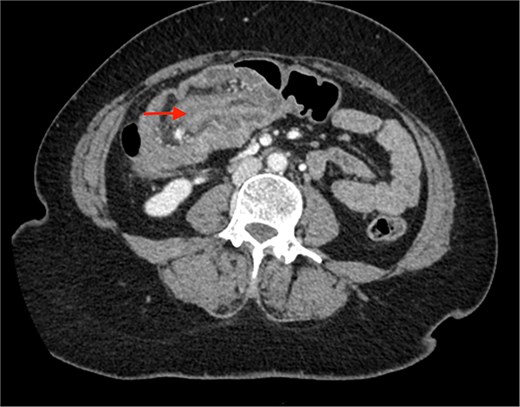

A CECT scan of the abdomen and pelvis revealed circumferential heterogeneously enhancing mucosal wall thickening involving caecum and ascending colon with pericolic fat stranding and ileocolic intussusception along with multiple enlarged heterogeneously enhancing necrotic lymph nodes in right iliac fossa and pericolic region (Figs 1 and 2).

Contrast enhanced CT of the abdomen showing an arrow pointing to the region of ileocolic intussusception.